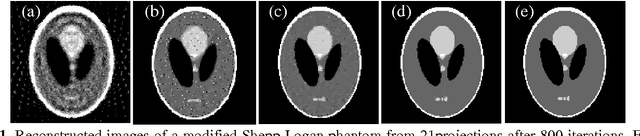

The L1-norm of the gradient-magnitude images (GMI), which is the well-known total variation (TV) model, is widely used as regularization in the few views CT reconstruction. As the L1-norm TV regularization is tending to uniformly penalize the image gradient and the low-contrast structures are sometimes over smoothed, we proposed a new algorithm based on the L0-norm of the GMI to deal with the few views problem. To rise to the challenges introduced by the L0-norm DGT, the algorithm uses a pseudo-inverse transform of DGT and adapts an iterative hard thresholding (IHT) algorithm, whose convergence and effective efficiency have been theoretically proven. The simulation indicates that the algorithm proposed in this paper can obviously improve the reconstruction quality.